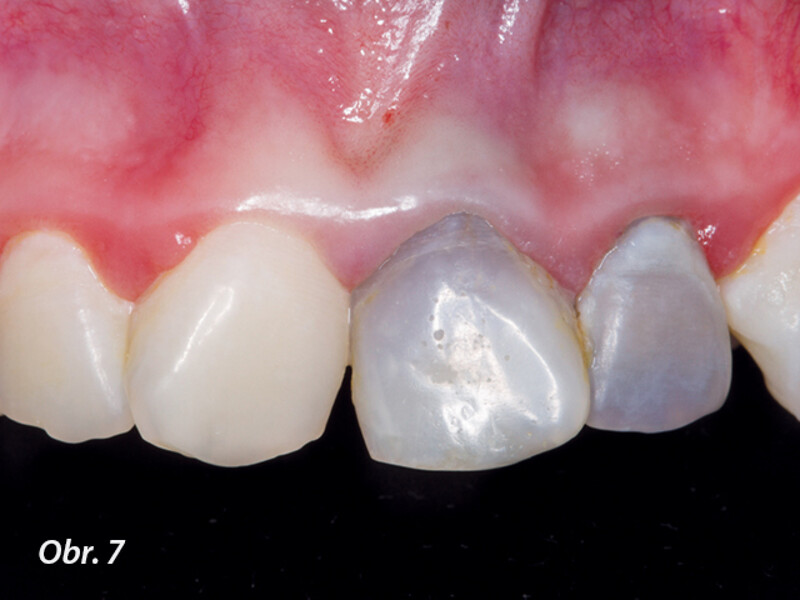

Indikační šíře MTA: Soubor kazuistik